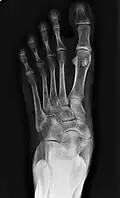

X-ray of the foot showing an accessory navicular bone

An accessory navicular bone is an accessory bone of the foot that occasionally develops abnormally in front of the ankle towards the inside of the foot. This bone may be present in approximately 2-14% of the general population and is usually asymptomatic.[1][2][3] When it is symptomatic, surgery may be necessary.